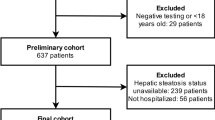

This is a retrospective study conducted at the Radiology Department of our Institution from March 30, 2020 to April 17, 2020. The study was approved by the Institution Ethics and Research Committee (Registration number 32622720.9.0000.5483). Informed consent was waived given the retrospective nature and characteristics of the study.

We included 411 consecutive patients with flu syndrome and clinically suspected of having COVID-19 infection who underwent both chest CT and RT-PCR for a case–control study. All CT examinations were performed in the same scanner, a Somatom Perspective 64-slice (Siemens Healthcare, Forchheim, Germany). The technical parameters used in the CT exams were: collimation 64 × 0.6 mm, gantry rotation time 0.48 s, recon slice width 8 mm, pitch 1.25, 110 KVp, mAs dependent on automatic modulation of the dose radiation (CARE Dose 4D by Siemens Healthcare).

From this number of patients, we excluded 11 patients who could have a bias in the liver assessment: three patients due to important artifacts in CT (the arms were lowered along the body), three patients who did not have a non-contrast-enhanced phase, two patients with polycystic liver disease, one patient with partial hepatectomy, one with right lobe hepatic atrophy due to portal venous thrombosis and one patient with liver transplantation.

The case group was composed by patients with a positive RT-PCR test for COVID-19 and the control group by patients with a negative RT-PCR test. However, as there is evidence that an early false-negative RT-PCR may occur in infected patients already showing CT manifestations of the disease (i.e., a positive CT) [10], to assure the criteria of negativity of the control group, we additionally checked all chest CT images of these individuals; those displaying CT findings within typical, atypical or indeterminate categories (according to the proposed reporting language for CT findings related to COVID-19 by the Radiological Society of North America (RSNA) [11]) were excluded, remaining only those who were considered ‘’negative’’. Further 84 individuals were excluded from the control group according to these criteria.

Finally, the case group (RT—PCR positive) was composed by 204 patients and the control-group (RT-PCR negative and chest CT negative pattern) by 112 patients, totaling 316 patients.